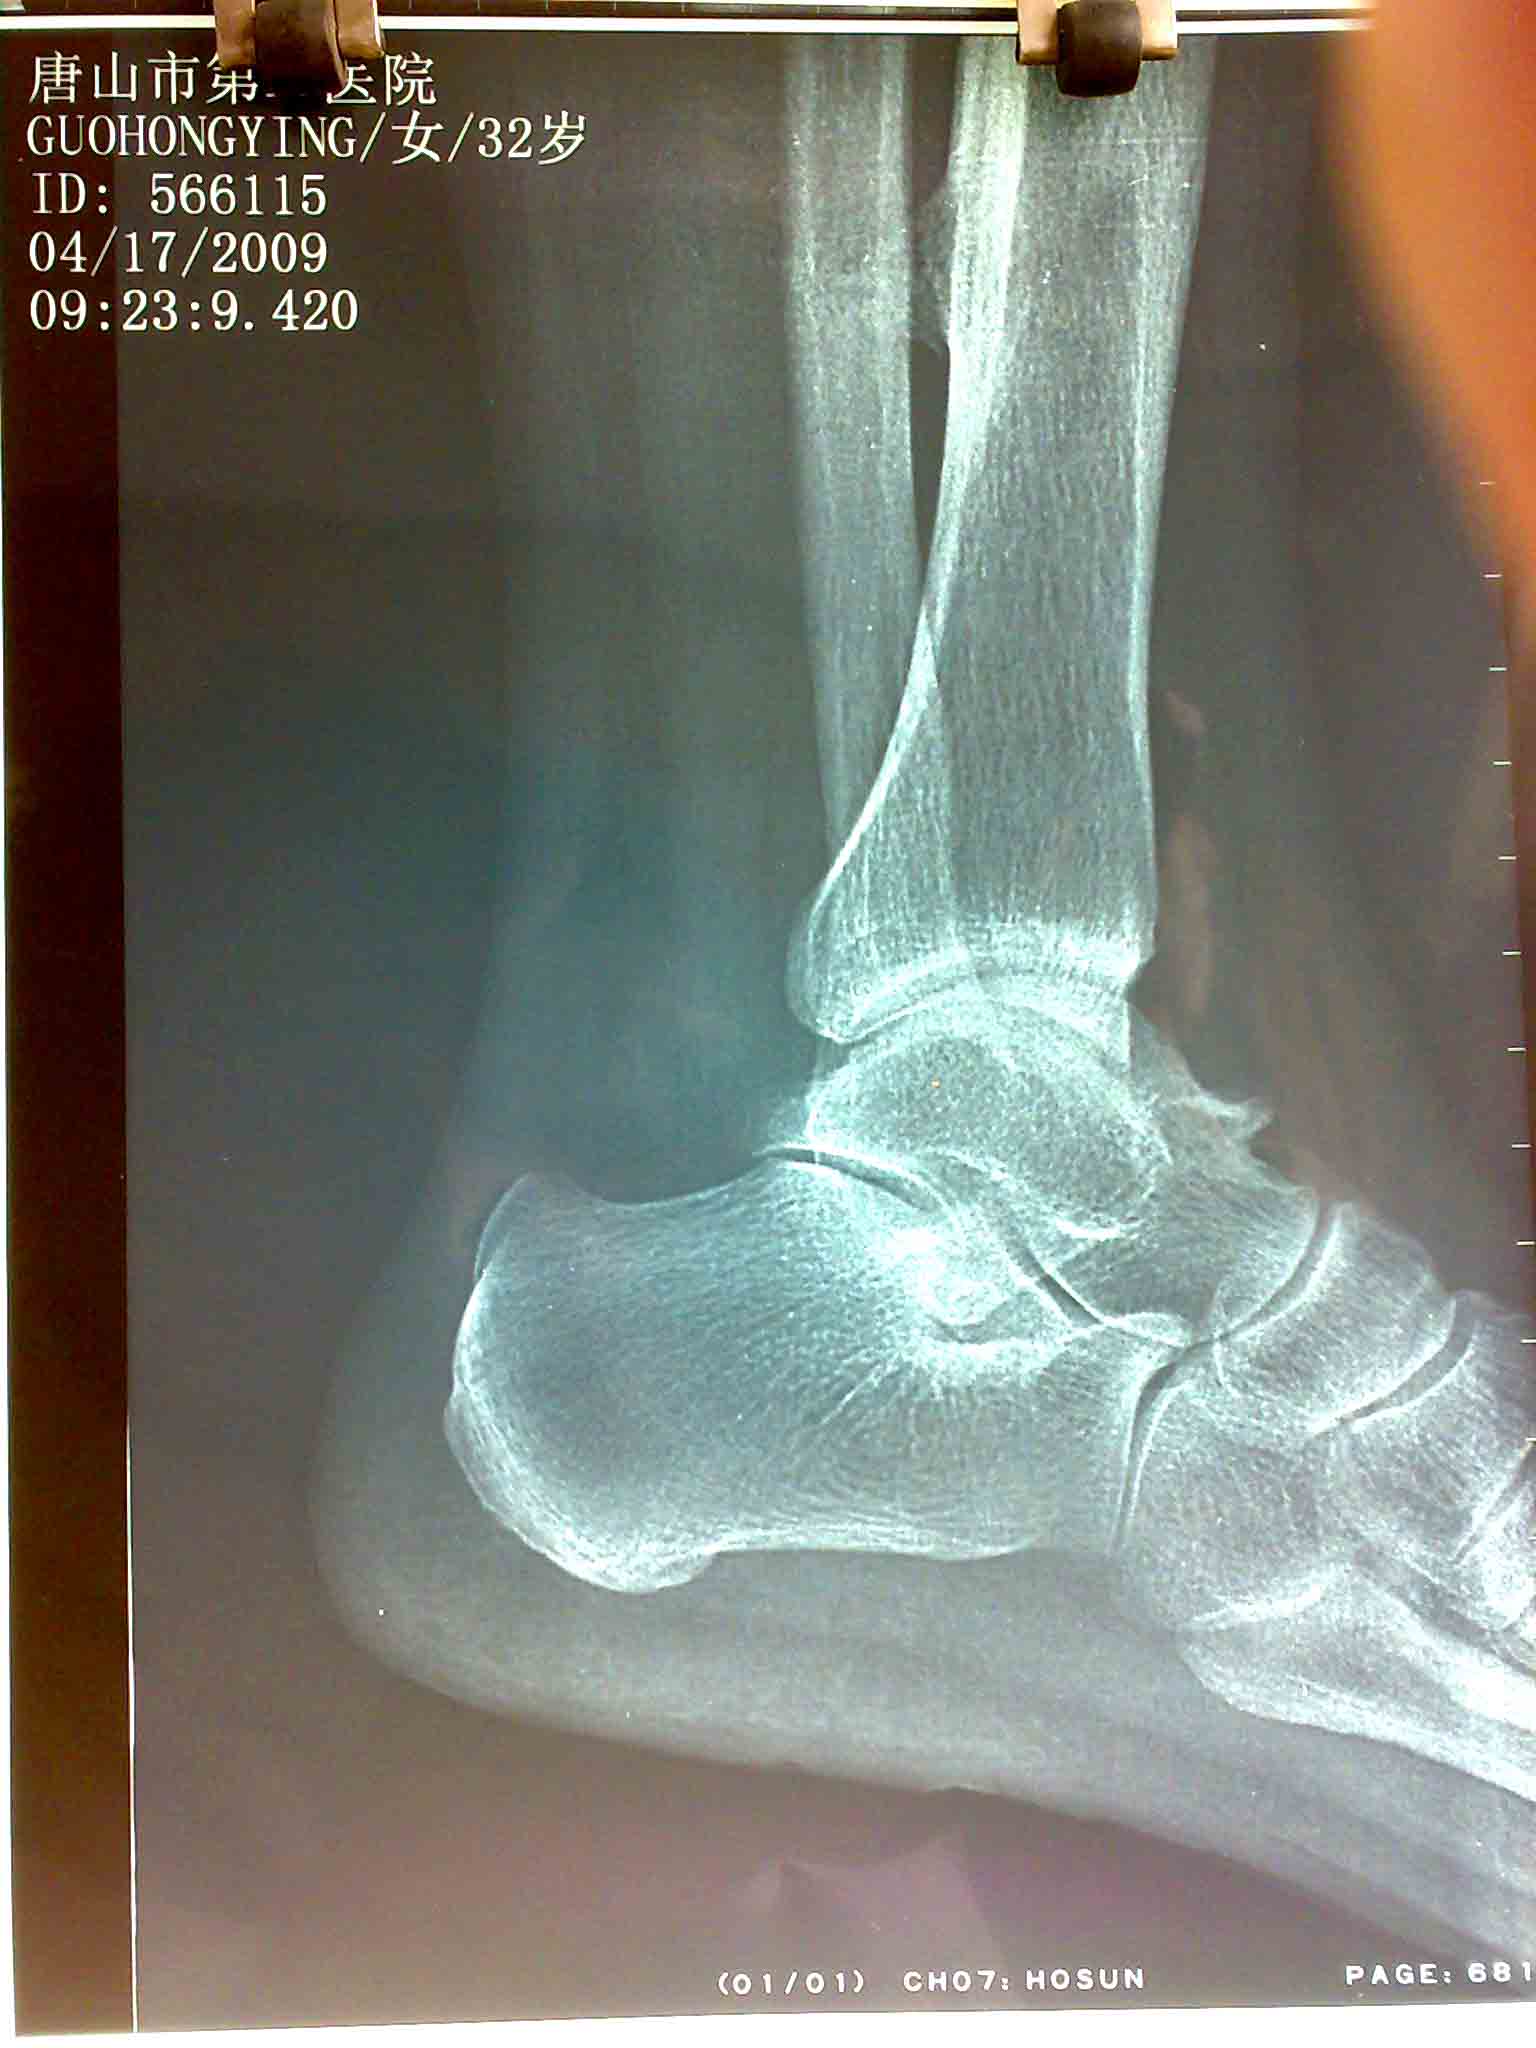

以下是引用zhangzhongshou在2010-7-8 6:43:00的发言:[br]1、胫骨下端骨软骨瘤;2、巨骨改变为巨骨嘴,属正常变异。(巨骨嘴,巨骨上缘可出现鸟嘴样骨性突起,为巨骨嘴,不要误认为骨质增生)。

以下是引用liaoqiang在2010-7-8 10:08:00的发言:[br]胫骨下段骨软骨瘤

以下是引用zhanggenliang在2010-7-8 21:37:00的发言:[br]胫骨下端骨软骨瘤,距骨嘴倒是第一次听说。学习了